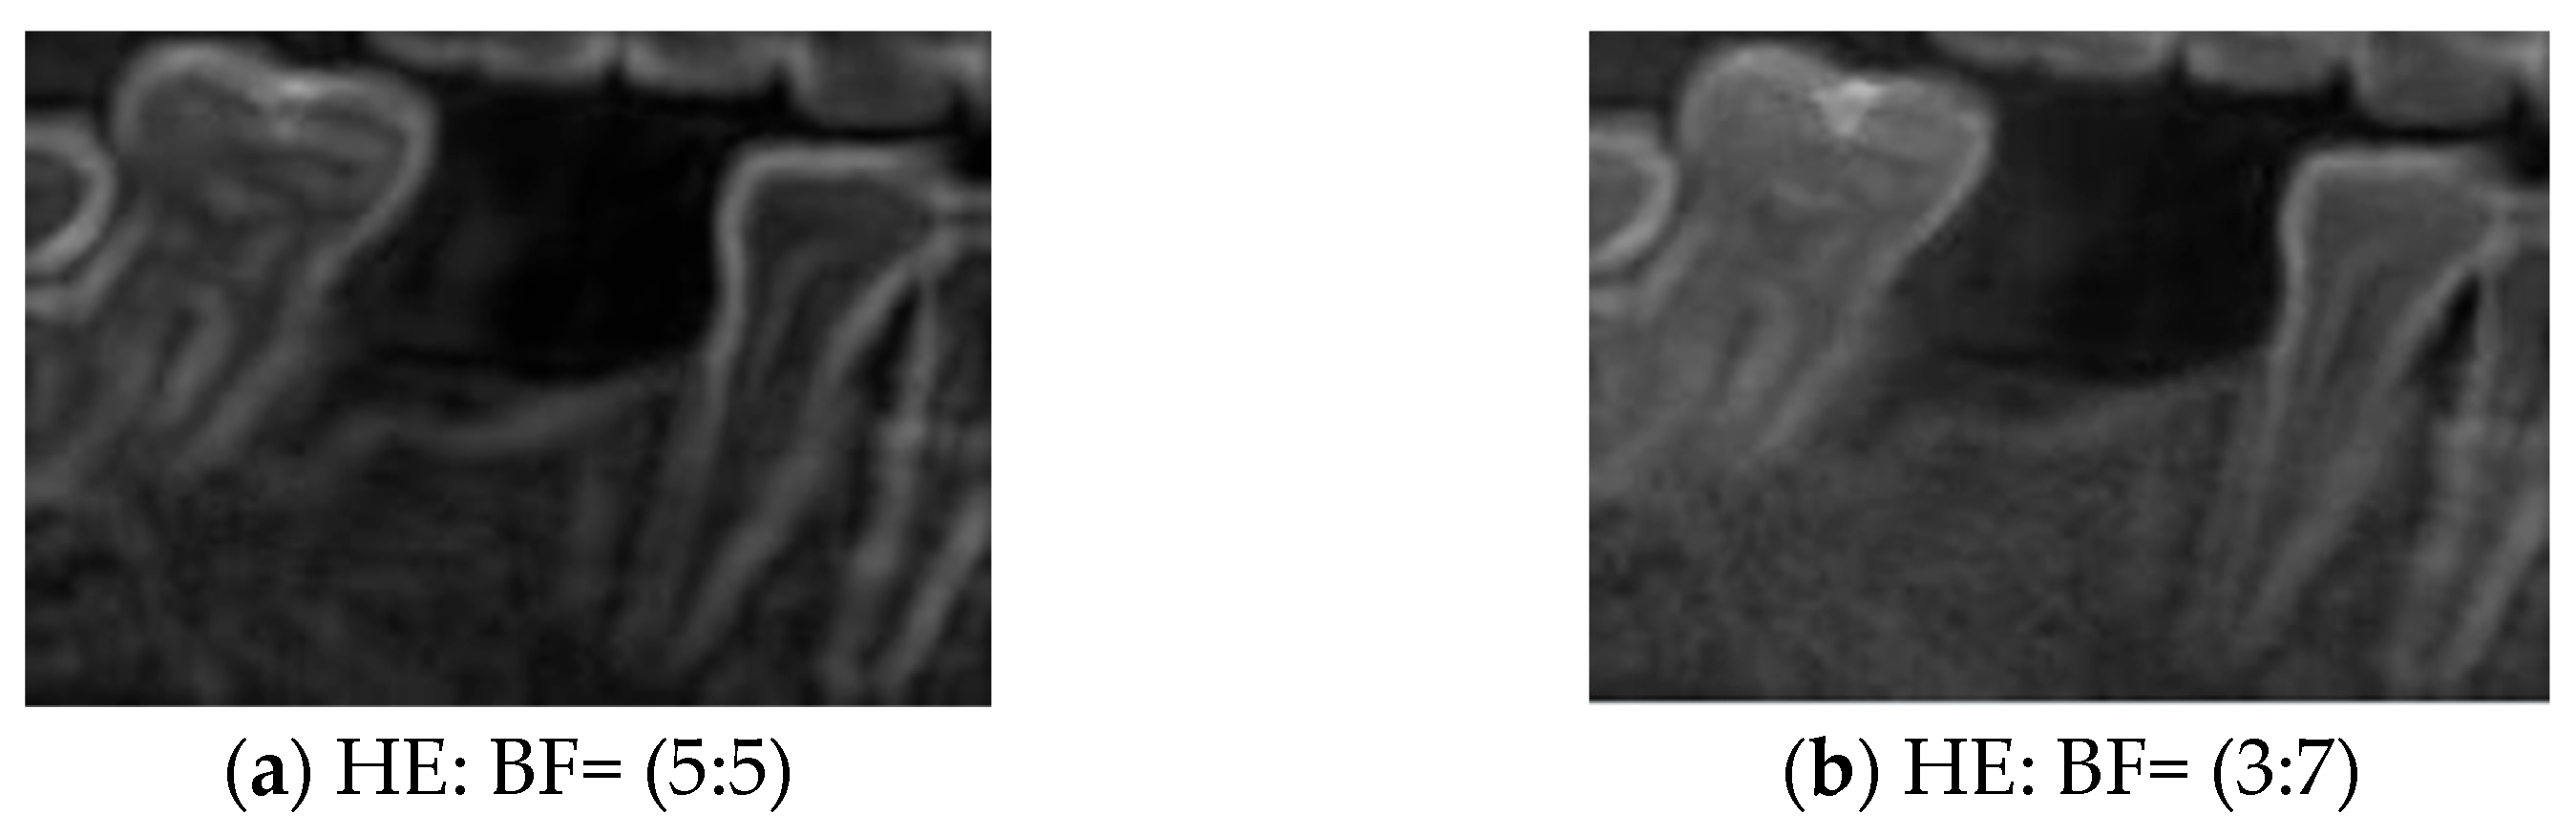

2.3.2. Histogram Equalization

Histogram Equalization (HE) was applied to address the issues of uneven contrast and brightness in the original images. HE is commonly used in image enhancement cases involving low contrast or concentrated grayscale distributions. The computational procedure typically involves calculating the grayscale histogram of the original image, deriving the cumulative distribution function (CDF), and using the CDF as a mapping function to generate the enhanced image. The principle of this method is to redistribute the pixel intensity values of the image, thereby achieving a more uniform distribution of grayscale levels [40]. This approach improved overall contrast and detail visibility in this study. The transformation function of HE is defined in (6). Specifically, represents the output grayscale value, is the original pixel value, L denotes the total number of gray levels, and is the probability of occurrence of the j-th grayscale level. This study used two categories of images for training: BF images and enhanced images obtained through image processing. By applying HE and blending it with BF images at varying degrees, composite images (HE: BF) were generated. This approach improves the model’s adaptability to diverse clinical conditions of dental morphology, thereby enhancing its generalization performance and robustness against interference, as illustrated in Figure 6.

Figure 6.

HE combines BF processing.